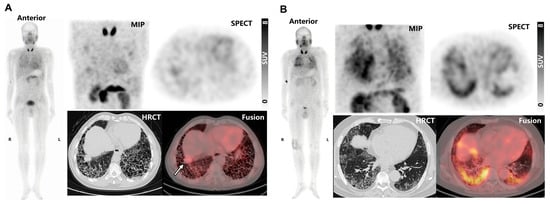

2.4. Uptake of 99mTc-H-PoFP2 in fILD Patients and Relationship with PFT and GAP Index